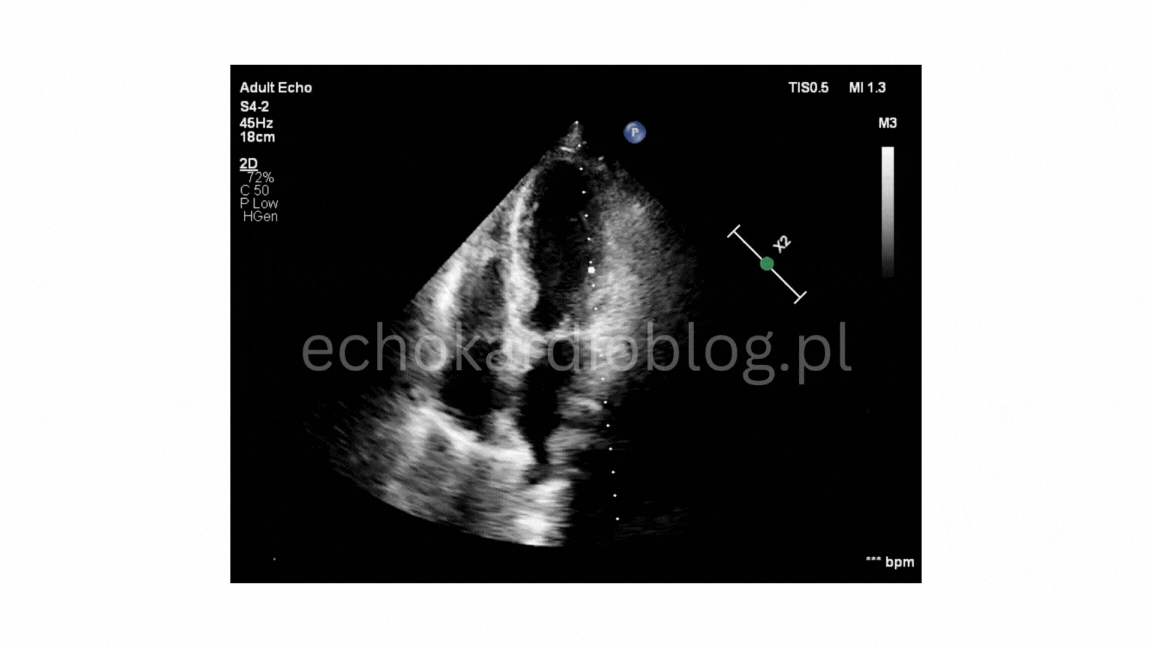

w EKG : tachykardia zatokowa, niezupełny blok prawej odnogi pęczka Hisa, fragmentacja zespołów QRS w odprowadzeniu II,III,aVF, niewielkie wklęsłe uniesienie odcinka ST w III, aVF, V5 i V6), odstęp Qtc w normie, a przede wszystkim echo serca , które wskazywało na Tako-tsubo. Rozpoznanie potwierdzono w koronarografii.

The diagnostic pitfall was the absence of a clear stressor, no chest pain, and markedly elevated D-dimers , which could initially suggest pulmonary embolism. However, further tests revised the diagnosis: elevated Troponins (966ng/l), ECG (sinus tachycardia , incomplete right bundle branch block, fragmented QRS complexes in leads II,III,aVF, slight ST-segment elevation in leads III,aVF, V5 and V6, normal Qtc interval ), and most importantly, echocardiography , which indicated Tako-tsubo cardiomyopathy . The diagnosis was confirmed by coronary angiography.